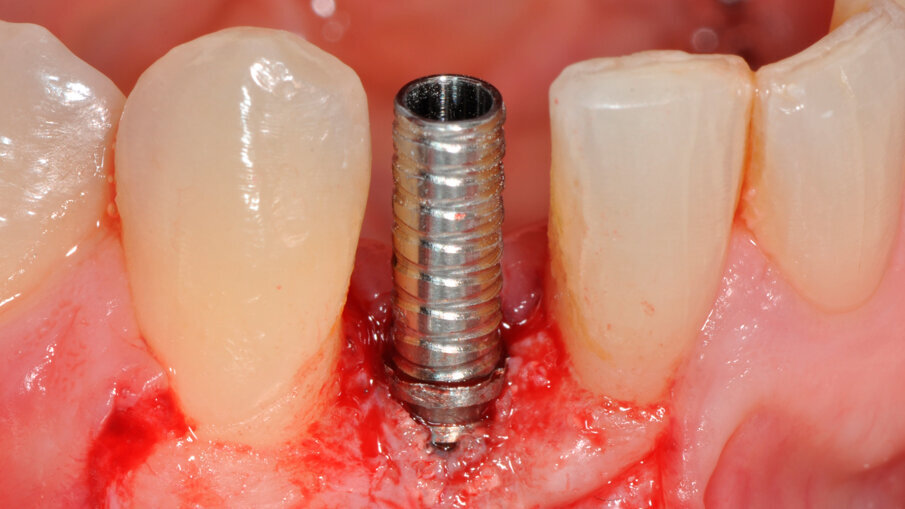

Zavedení implantátu

V rámci prvního kroku zavádění implantátu byly pomocí chirurgické šablony vyhodnoceny biologické aspekty podle pravidla 3A-2B (obr. 3). První pozice pro vrtání byla vyznačena tak, aby bylo dosaženo 2B a zajištěn úhel osteotomie pomocí vrtáku Precision Drill EV (Dentsply Sirona). Úhel byl potvrzen a osteotomie v hloubce pro implantát byla preparována pomocí vrtáku Twist Drill EV (Dentsply Sirona; obr. 4). Hloubka osteotomie byla zkontrolována pomocí nástroje Implant Depth Gauge EV (Dentsply Sirona (obr. 5). Poté byl zaveden implantát OsseoSpeed EV 3.6 o délce 11 mm (obr. 6). Předpokladem bylo, že zbývající aproximální kost poskytne oporu aproximální papile. Periapikální RTG snímek pořízený bezprostředně po zavedení implantátu potvrdil, že implantát není v kontaktu s žádným ze sousedních kořenů (obr. 7). Poté byl za použití otiskovací kapny Implant Pick-up Design EV (Dentsply Sirona), což je samonaváděcí otiskovací komponenta, která se umisťuje do implantátu, pořízen otisk, jehož účelem bylo získání informací o pozici implantátu (obr. 8). Provizorní abutment Temporary Abutment EV byl upraven v oblasti krčku tak, aby se zabránilo kontaktu s aproximální kostí a bylo možné správné dosednutí (obr. 9). Za použití kofferdamu pak byla pryskyřicí ihned upevněna provizorní náhrada (obr. 10). Poté byla náhrada sejmuta, dokončena, vyleštěna a za lehkého přitlačení opět nasazena.